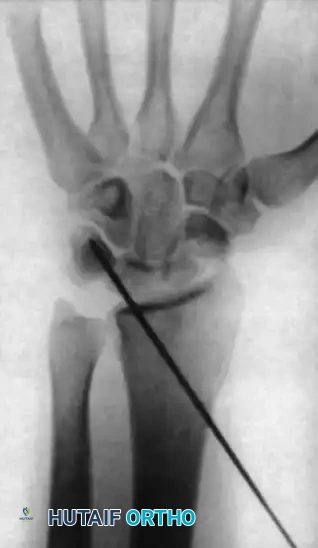

FIGURE 69-42 B: Posteroanterior radiograph demonstrating the Kirschner wire placed percutaneously through the radial side of the radius into the lunate, locking it in the corrected position.